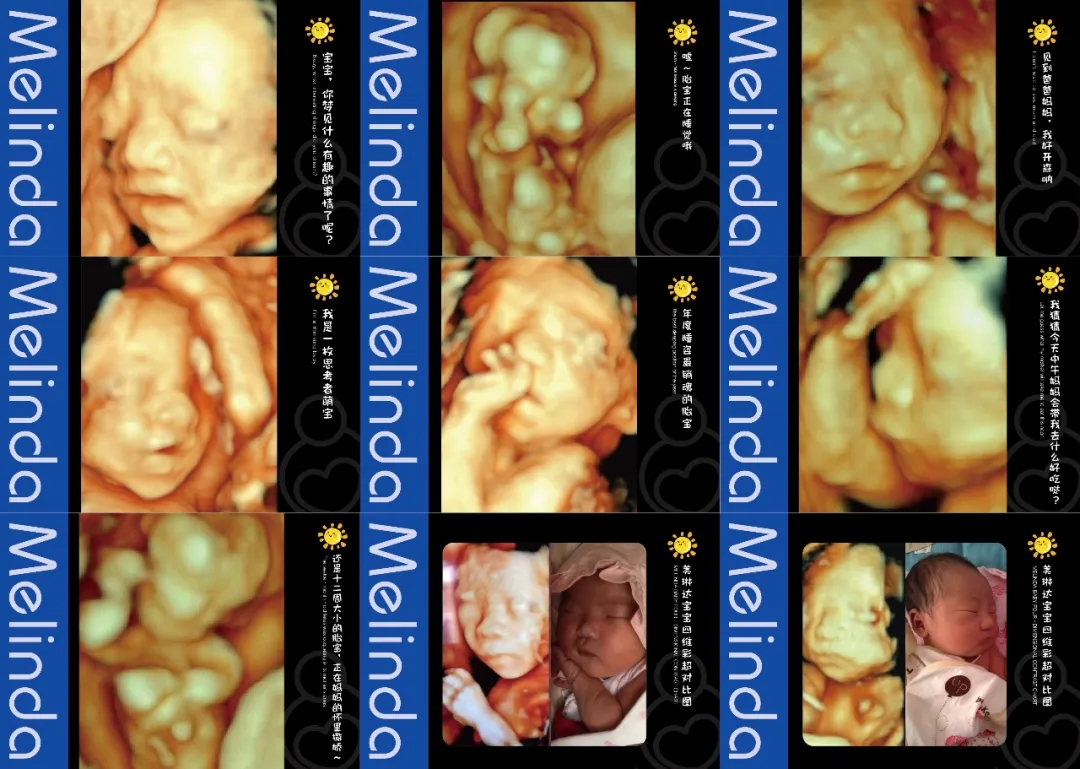

(美琳达四维宝宝照片)

注重孕妈体验度-检查更舒适入院时,导医客服引领陪同检查,检查结果出来后专人电话通知。候诊时,大厅放置舒适的沙发可供休息,客服也会为客户提供饮品和食品等。检查时,四维彩超诊室设置适宜观看的高清电视屏幕,双屏互动模式,检查时孕妈可以清晰看见医生操作。检查床旁放置舒适纯皮沙发,支持家属陪伴检查。重要的是,美琳达也会提供胎儿写真照片,留作纪念。

(明星主播东玥两次四维检查胎宝照片对比)